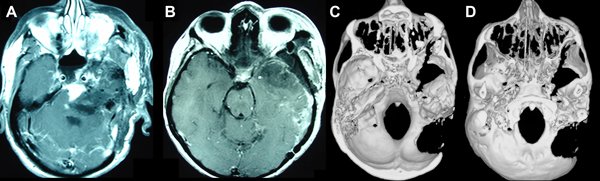

Se presenta en consulta, acompañado por su familia, un paciente masculino de 54 años de edad, deambulando por sus propios medios. Como antecedentes presenta 4 intentos de resecciones quirúrgicas de un meningioma petroclival izquierdo de aproximadamente 4 centímetros de diámetro. Los procedimientos fueron realizados en un período de 7 años por dos equipos diferentes y en dos instituciones distintas. En todos los casos se optó por la vía suboccipital lateral izquierda retrosigmoidea y en la última ocasión se le realizó una extensión temporal posterior. Los controles por imágenes post operatorios demostraron la persistencia de la lesión con prácticamente su volumen inicial (Figura 1). La Anatomía Patológica de la lesión arrojó como resultado un meningioma transicional (grado I de la WHO). Luego del último intento de resección, se le indicó tratamiento radiante, recibiendo dosis completa de 6000 rads de acelerador lineal en conformación hipofraccionada. Concurre a la consulta 20 meses después del último procedimiento quirúrgico y 17 meses después de finalizar el tratamiento radiante. No recibió tratamiento quimioterápico. Como secuela de los múltiples tratamientos previos, el paciente presentaba pérdida completa de la audición del lado izquierdo, demostrado por métodos electrofisiológicos, una paresia facial izquierda moderada (Grado III de House-Brackmann), compromiso leve de la deglución que no requería conductas activas. Debido a los múltiples intentos de abordar a esta lesión por la vía retrosigmoidea clásica4 (uno de los mismos presentó una extensión subtemporal5), y la posterior irradiación de la zona, los autores se plantearon la disyuntiva entre abordar a esta patología por la vía presigmoidea, utilizando alguna de sus variantes conservadoras y/o reconstructivas6,7, o intentar una resección tumoral buscando una entrada quirúrgica libre de las secuelas propias que dejan los procedimientos previamente realizados. Se optó por esta última posibilidad.

Figura 1. A) RMN, ponderación T1, con gadolinio, corte axial. Se observa la persistencia del meningioma petroclival izquierdo y las huellas de los procedimientos quirúrgicos previos. B) RMN, ponderación T1, con gadolinio, corte coronal. Se observa la persistencia del meningioma petroclival izquierdo después de los procedimientos quirúrgicos previos. C) Tomografía computada, corte axial, ventana ósea, reconstrucción 3D. Se observa la craniectomía suboccipital lateral izquierda, retrosigmoidea con extensión temporal, utilizada en las 4 ocasiones quirúrgicas previas.